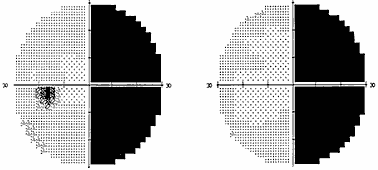

В силу различных причин, в частности, из–за строения диафрагмы турецкого седла, опухоль может распространяться не столько кверху, сколько латерально, в сторону кавернозного синуса – латероселлярный рост. Зрительные нарушения, которые присутствуют при этом росте опухоли, чаще представлены асимметричным хиазмальным синдромом со значительным, вплоть до практической слепоты, понижением остроты зрения на одном глазу. Может также развиться одноименная (односторонняя) гомонимная гемианопсия (рис. 2) в результате воздействия опухоли на зрительный тракт. Дефекты поля зрения появляются в половине поля зрения на стороне, противоположной локализации опухоли. Офтальмологи должны быть внимательны, поскольку дефекты поля зрения при латероселлярном росте опухоли и развитии асимметричного хиазмального синдрома или гомонимной трактусной гемианопсии появляются в носовой половине поля зрения на глазу на стороне преимущественного роста опухоли (рис. 3). Это может спровоцировать ошибочную диагностику глаукомы.

Рис. 2. Полная правосторонняя гомонимная гемианопсия (автоматическая статическая периметрия)

Рис. 3. Начальная левосторонняя гомонимная гемианопсия (автоматическая статическая периметрия)